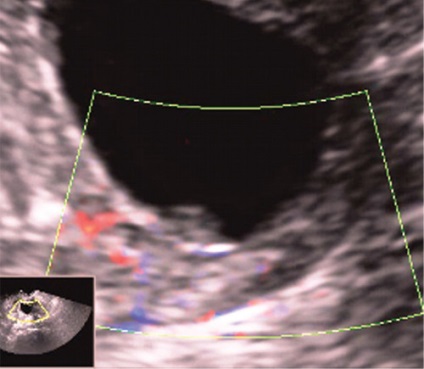

Érintkezése során ehometrosalpingografii alkalmazásával végzik, mint kontraszt steril sóoldatban is lehetővé válik láthatóvá a kis polipok az endometrium és az endometrium összenövések (ábra. 3). Az akusztikus alapja a lehetséges nem-invazív és ehogisteroskopii ehotservikoskopii teremt serometra, például posztmenopauzális elzáródás külső os (ábra. 4), vagy, amint azt a fentiekben megjegyeztük, a fokozott nyálka termelődés a cervikális végén a proliferatív fázis a menstruációs ciklus. Mivel a váladék az időszakban bizonyos esetekben állnak vizualizációs és polipok, lokalizált a külső os. Hematometra és / vagy gematotserviks, mert a szervezet folyamatai vérrögök kevésbé informatív, mint ennek fényében fibrin vérrögök és polipok nehéz lehet megkülönböztetni a normál B-mód (ábra. 5, 6).

A különböző szállítási módok és a Doppler véráramlás képalkotó nedopplerovskoy valóban lehetővé teszi számunkra, hogy azonosítsuk a vaszkuláris kocsány a polip (ábra. 9), kivéve, ha nincs jele a hámlás az endometrium. Ebben az esetben a (ábra. 10) mozgását a vér az üregben a méh és a méhnyak lehet szimulálni a vér áramlását az erek a polip lábak és regisztrált a készülék kijelzőjén, mint egy hasonló színjelek.

Ábra. 9. A kocsány nyaki polip CDM módban.